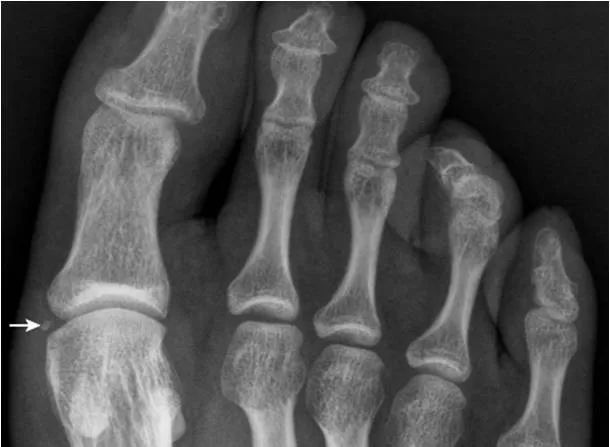

31.第5跖骨粗隆骨折:

第5跖骨粗隆处见横行、纵向透亮线,横行透亮线(箭)为骨折线,纵向透亮线(箭头)为骨骺与骨间的软骨连接投影。撕脱骨折线为横行走向是与骨骺连接线的重要鉴别点。(右图,女,5岁;左图,男13岁)